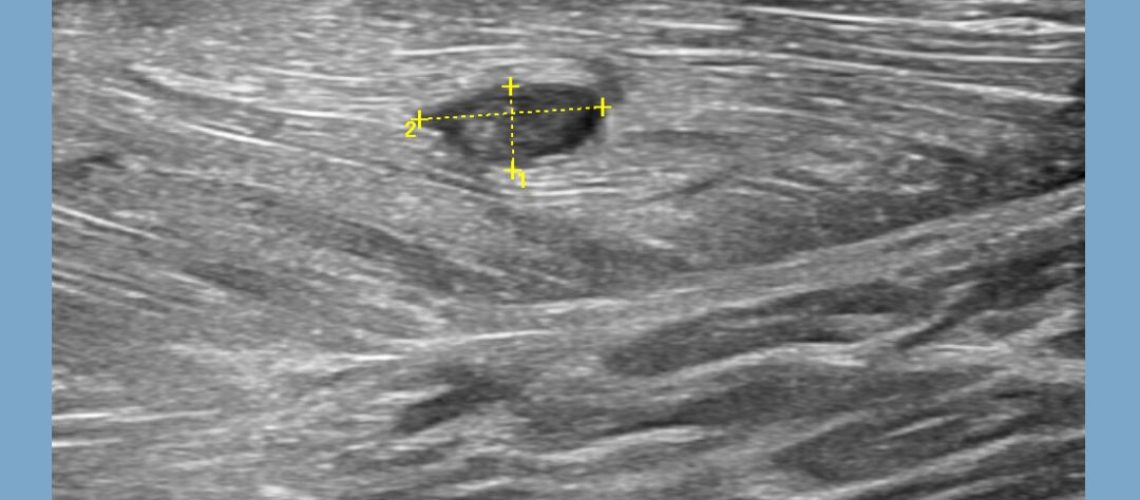

Aquí tenéis el ejemplo de un jugador de fútbol juvenil que recibió esta nueva temporada un traumatismo directo en el gemelo interno causándole una rotura fibrilar.

En la siguiente imagen ➡️ podrás observar como visualizamos a través de nuestro ecógrafo perfectamente la rotura 🦵🏼🖥️